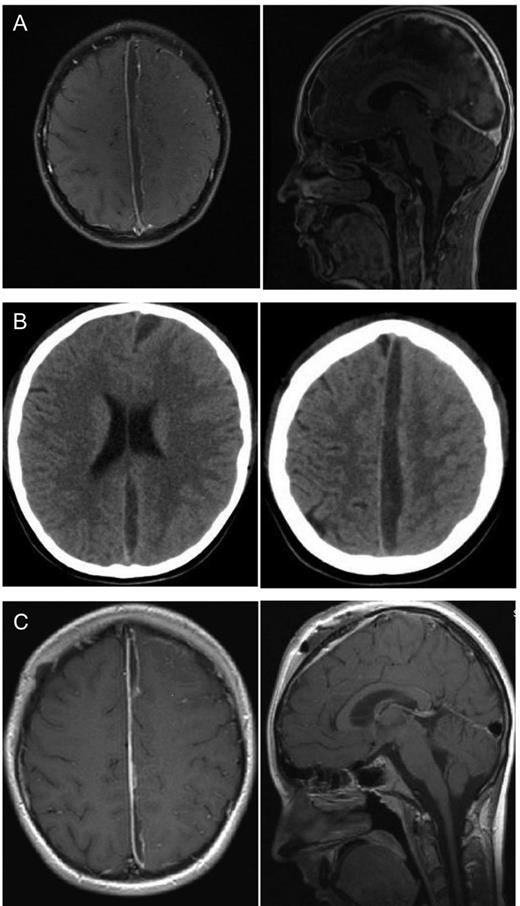

An 8-year-old girl with a diagnosed sinusitis frontalis, already under antibiotic therapy, developed progressive headaches and increasing infection parameters. The brain MRI showed a subdural frontal parafalcine empyema (Fig. 2A). The girl's symptoms were nausea, emesis, headache and fever but no neurological disturbance. We drained the empyema by a right frontal craniotomy and clear the abscess cavity with isotonic saline solution. The brain extended rapidly after removing the space-occupying pus. Microbiologically, streptococcus intermedius infection was verified. The antibiotic therapy was optimized after resistogram. After surgery, the girl's condition got worse with seizures and fever. In a repeated MRI (Fig. 2B), the subdural empyema showed an enlargement. We decided to revise and extend the approach to remove the capsule of the empyema which could be seen perioperatively. The empyema was released by an osteoplastic right parasagittal trepanation.

Eight-year-old girl with parafalcine subdural empyema. (A) Axial and sagittal MRI section with administration of gadolinium. Space occupying empyema with the largest expansion right frontal and contact to the falx. Perifocal edema without a significant midline shift is seen. (B) Axial and sagittal MRI section with administration of gadolinium. An enlargement of the empyema is visible after first surgery. The empyema is localized in central parasagittal region with a significant space-occupying component with a compression of the right central region. (C) Axial and sagittal MRI section with administration of gadolinium. A regression is visible after second surgery. In comparison to preoperative MRI, a notable decrease in the space-occupying part of the empyema is seen.

The symptomatic epilepsy was treated with levetiracetam. Afterwards, the girl stayed for another week in our department. At the day of discharge, an MRI (Fig. 2C) was repeated and showed a regressive parafalcine abscess. The infection parameters decrease steadily under antibiotics and no seizures were noticed anymore. An MRI was performed 3 months after second surgery. After the last MRI, the antibiotic and the antiepileptic therapy were stopped.